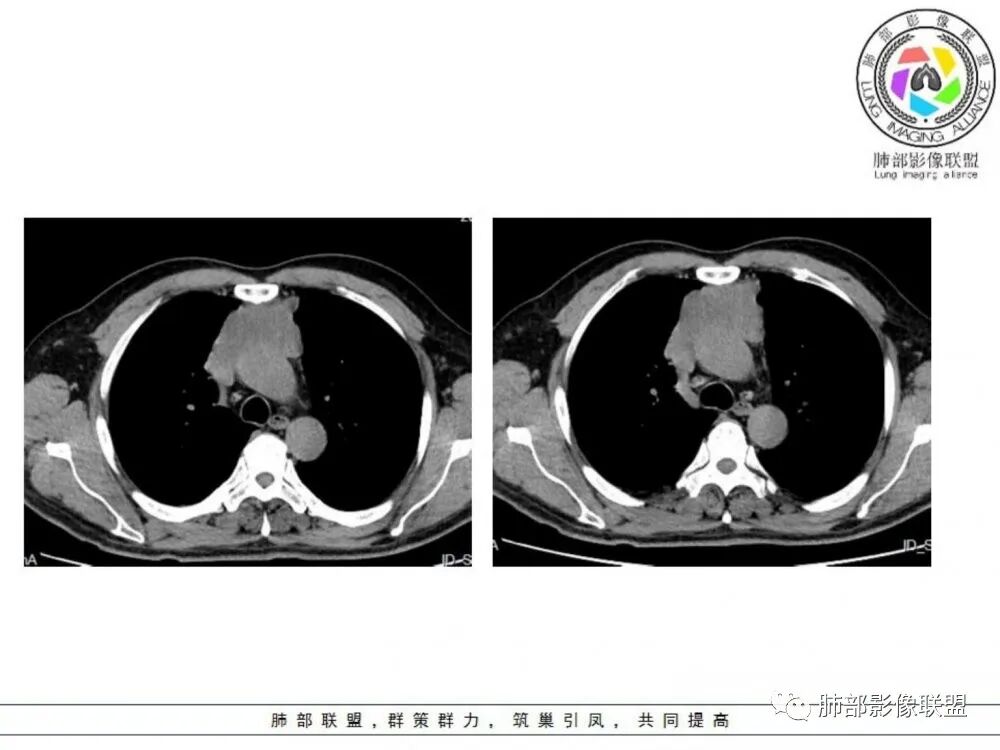

男性患者,65岁,前胸后背疼痛一个月。影像学前上纵隔分叶状的软组织肿块,肿块形态怪异,偏软,位于大血管间隙前,并有向血管后间隙发展的趋势,平扫CT值为40左右,增强扫描中心部未见强化,周围轻度的强化,约为50左右。前上纵隔的疾病谱包抬胸廓内甲状腺肿、胸腺瘤/癌、畸胎瘤、淋巴瘤。少见的心包囊肿或支气管囊肿。根据肿块的形态及强化特点,首先还是排除了胸内甲状腺肿及胸腺来源的肿物,这类的肿物强化比较明显。畸胎瘤成分比较复杂,具有软组织钙化或者脂肪类的组织,这个肿物虽然在平扫的时候好像有斑点状的钙化灶,但是总体成分还是比较单一,所以还是排除畸胎瘤的诊断。所以这样的情况是考虑:淋巴类的肿瘤,注意排除心包的囊肿或支气管来源的囊肿。

老年男性患者,前膈软组织肿块,边缘轮廓不光整,边界似乎尚清晰,内见小点状钙化灶,平扫密度欠均匀,增强后轻度强化表现,边缘有些斑片状的高强化区。综合考虑胸腺瘤或胸腺鳞癌,神经内分泌癌强化弱了一些。患者年龄较大,生殖细胞肿瘤不考虑,淋巴瘤血管包绕不够,可能性不大

老年男性,前胸后背痛一个月,前纵隔不规则肿块,分叶,向纵隔血管间隙进入,且与纵隔血管分界不清,增强边缘轻度强化,中间可见无强化区,似见点状钙化,PET为高代谢,考虑为来源于胸腺,胸腺瘤或胸腺鳞癌可能

老年男性,定位前纵隔,似乎有点塑形生长,肿块与大血管分界欠清,上腔静脉局部包绕受压,侵犯?增强扫描低强化。考虑恶性,胸腺癌可能。鉴别淋巴瘤。

老年男性,前纵隔不规则软组织肿块影,密度欠均匀,与大血管分界欠清,上腔静脉局部包绕受侵,增强扫描不均匀轻度强化,PET-CT高代谢。考虑恶性肿瘤性病变,胸腺癌可能。鉴别淋巴瘤。

前纵隔胸腺区分叶状软组织肿块影,轻度不均匀强化,中心可见坏死,边缘不清,病灶与邻近心包见条索影,上腔静脉受侵,上纵隔多发小淋巴结,考虑胸腺鳞癌可能。

老年男性,前纵隔肿块,形态不规则,右侧内乳动脉增粗,与血管脂肪间隙模糊消失,定性恶性,周围多发小淋巴结,有斑点状钙化灶,增强中心低密度区无强化,边缘强化为主,首先考虑胸腺鳞癌,鉴别胸腺瘤。

中老年男性,前纵隔占位,基本居中,向两侧生长;边缘膨隆分叶,部分边界不清,增强不均匀轻中度强化,坏死区边界不清;周围多发增大淋巴结,考虑恶性。主要在胸腺癌、胸腺瘤、淋巴瘤之间鉴别。病灶偏软,有钻缝样生长,这些征象偏向于淋巴瘤。但此例老年患者,病灶内有点状钙化,缺乏结节堆砌感,倾向胸腺癌诊断。